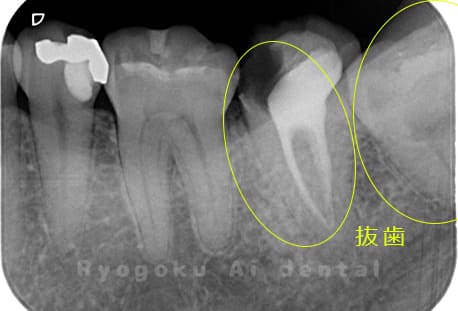

他院で右下の根の治療を行い、セラミックを被せる説明をされていたが、根の治療が終わらないため転院された患者さんです。隣の親知らずの抜歯の必要性と、根の治療を行なっている歯牙の予後が悪いため、移植治療を提案し、右下の親知らずの抜歯と同時に、右下の奥歯(7番)への移植治療を行いました。被せ物を行う必要もなく、順調に経過してます。